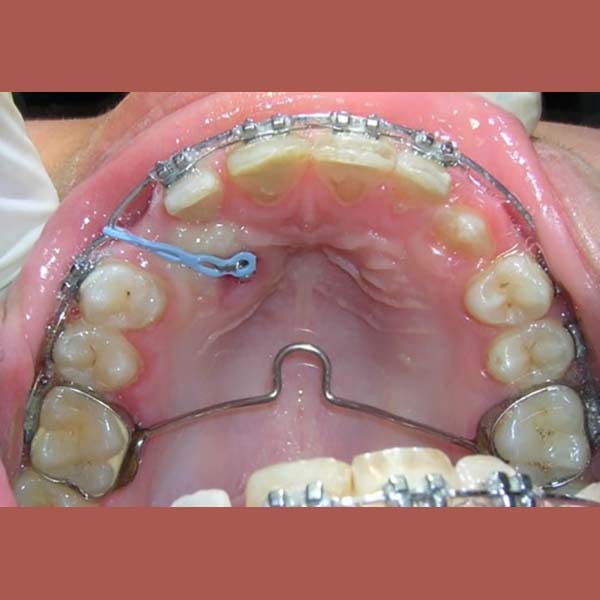

AFTER

بعد التشخيص الدقيق، وضع الدكتور خالد الكاتب خطة علاجية من مرحلتين باستخدام تقويم الأسنان:

كما تظهر الصور، تم إنزال الناب المنطمر بنجاح ورصفه بشكل مثالي مع بقية الأسنان. النتيجة هي ابتسامة كاملة وصحية، واستعادة سن مهم جداً لوظيفة الفم وجمال الابتسامة.